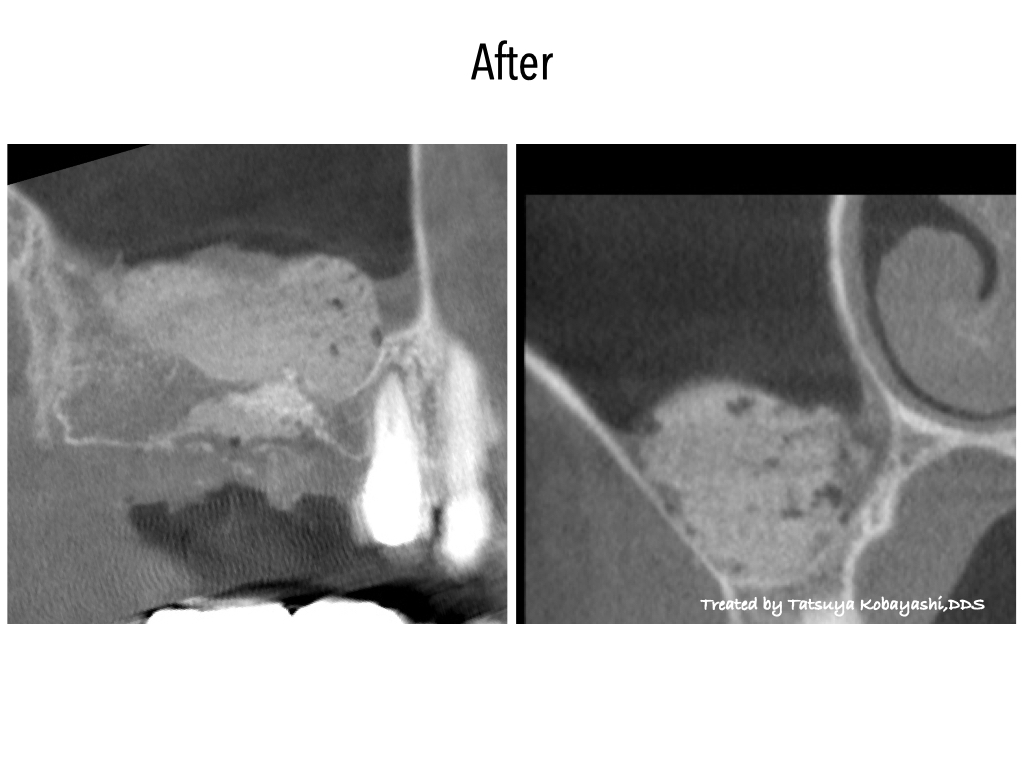

サイナスリフトとは、上あごの骨の高さが足りずインプラント治療が難しい場合に、上あごの奥にある「上顎洞(じょうがくどう)」と呼ばれる空洞の底を持ち上げて骨を造成する手術です。手術でできた空間に骨補填材などを充填し、骨が再生・定着するのを待ってからインプラントを埋め込みます。

骨の厚みが大きく不足している場合にもインプラント治療が可能になります。

| 治療内容 | 右側サイナスリフト |